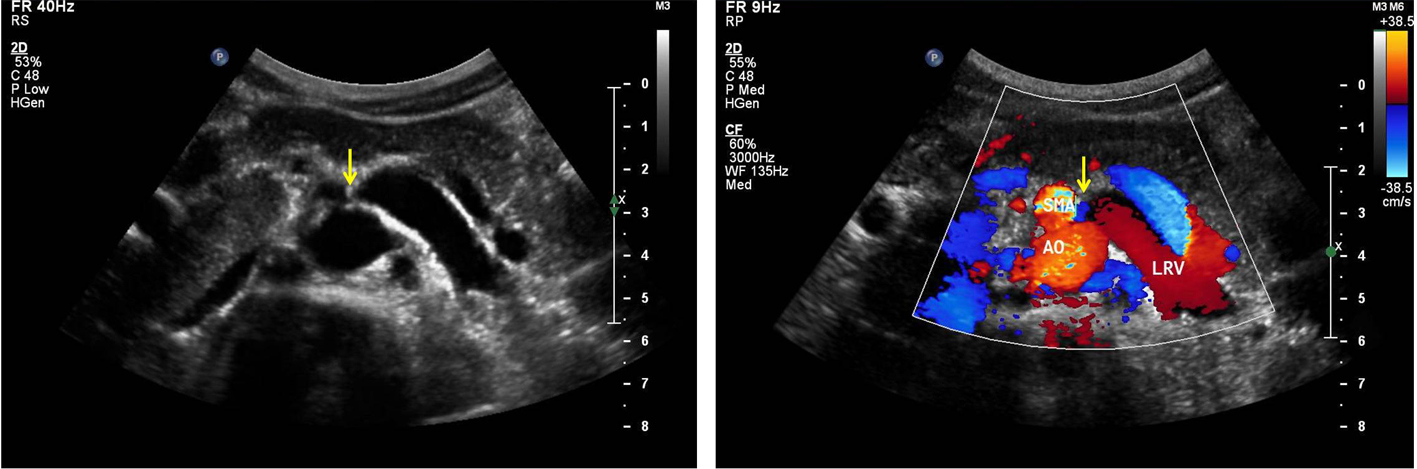

A 26-year-old man visited our institution for evaluation of proteinuria. He intermittently presented with acute urinary retention. Other urological evaluations were unremarkable. Urinalysis exhibited trace proteins without hematuria. Renal duplex and enhanced computed tomography (CT) of the abdomen and pelvis were performed. The duplex ultrasound typically demonstrated aortomesenteric anatomy with entrapment of the left renal vein (LRV) (Fig. 1). The diameters of the LRV at the hilar and aortomesenteric portions were measaured as 11 mm and 1.2 mm, respectively. The duplex ultrasound also indicated a significantly higher ratio of the peak systolic velocity (PSV) to the hilar renal vein PSV at the point of renal vein compression (> 6). This observation demonstrates the diminished volume of flow and dampened pulsatility upon spectral analysis of the left renal vein. Enhanced CT angiography revealed compression of the left renal vein between the aorta and the superior mesenteric artery (Fig. 2). The Nutcracker syndrome is defined as a rare cause of hematuria and flank pain caused by compression of the left renal vein between the aorta and the superior mesenteric artery where it passes at the point of bifurcation of the arteries [1]. The observed compression causes venous hypertension and the formation of renal venous collaterals leading to the subsequent rupture of the septum between the veins and the collecting system, and finally, resulting in hematuria and flank pain [2, 3]. In this particular patient case, although rare, the nutcracker should be included as the potential cause of proteinuria in addition to hematuria in the absence of other renal diseases.

![]() Click for large image | Figure 1. The duplex ultrasound typically demonstrated aortomesenteric anatomy with entrapment of the left renal vein (LRV). |